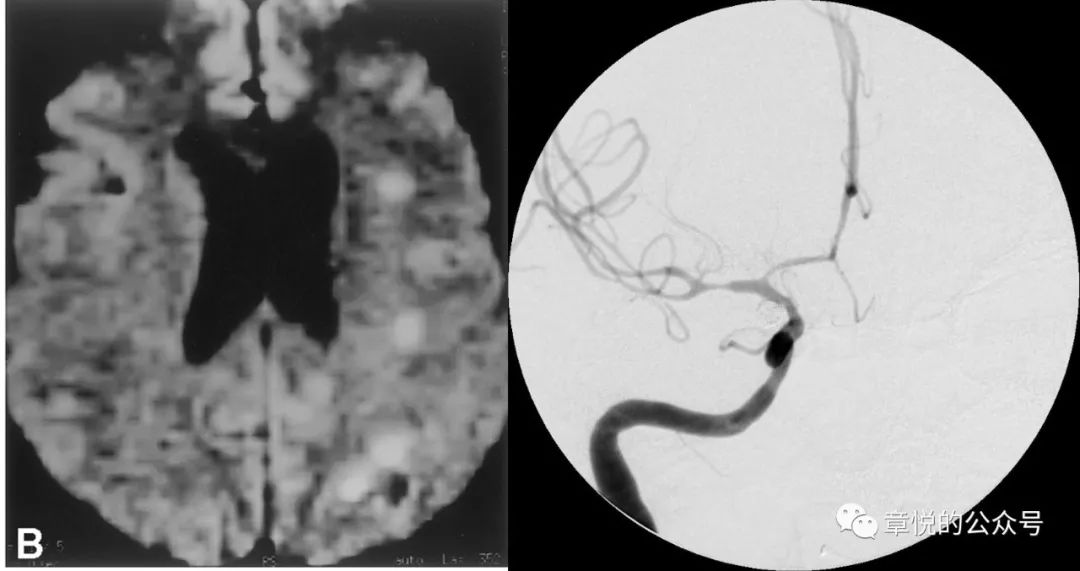

硬膜下血肿如破入蛛网膜下腔可导致蛛网膜下腔出血,蛛血引起的急性血管痉挛常在半小时以内出现,表现为头痛、局灶神经体征或一过性意识障碍;而迟发性血管痉挛常发生于出血的第3天,症状最严重为第6-8天,可持续2-3周,表现为头痛、意识障碍和/或局灶神经系统症状,血管造影可见血管痉挛收缩,MRI的弥散加权相(DWI)可见多发小梗死病灶。(图3)不过我们这个病例并不符合上述影像表现:MR并未见到梗死病灶;CTA也没见到血管痉挛;而腰穿直接否定了血管痉挛的前提——蛛网膜下腔出血,腰穿连一个红细胞都没捞着。

图3. 蛛网膜下腔出血导致的血管痉挛及DWI相所见的病灶